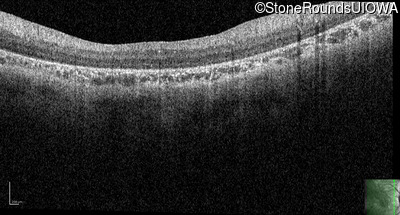

Optical Coherence Tomography - Right - 10/300 sc

Exemplar / OCT Stack